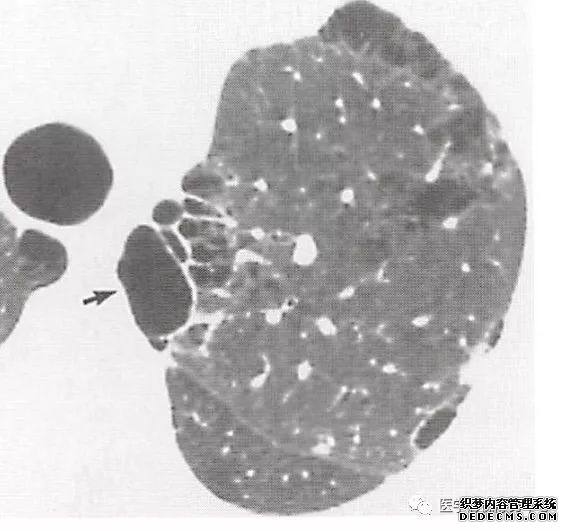

肺内淋巴结的CT表现特点及与病理对照